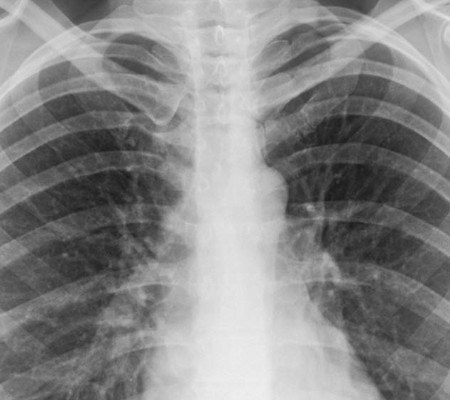

Segundo assessoria, o proprietário da Delta Laticínios, encontra-se em tratamento de uma grave pneumonia pelo vírus Influenza H1N1.

O empresário natural de Minas Gerais, mas que mora em Parnaíba, Oderman Bittencourt, proprietário da Delta Laticínios, está encontra-se em Teresina em tratamento de uma grave pneumonia pelo vírus Influenza H1N1. Por meio de nota, a assessoria do empresário informou ainda que o mesmo está reagindo bem ao tratamento e que logo retornará as suas atividades, esclarecendo que os exames médicos testaram negativo para  infecção por Coronavírus (Covid-19).